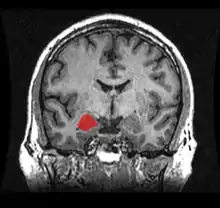

MRI coronal view of the amygdala

MRI coronal view of the right amygdala